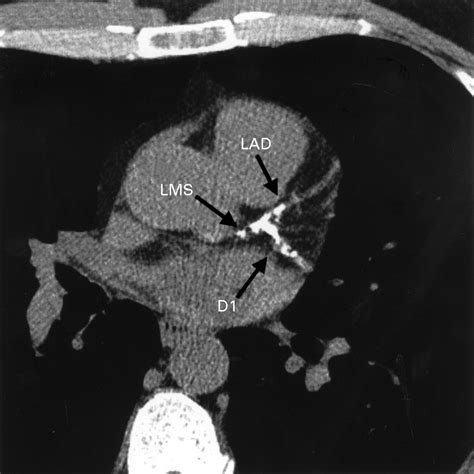

Coronary Artery Calcium scoring is a specialized type of computed tomography (CT) scan that focuses on the heart. Unlike traditional CT scans, CAC scoring specifically looks for calcium deposits in the coronary arteries. These deposits are a sign of atherosclerosis, a condition where plaque builds up in the arteries, narrowing them and increasing the risk of heart attacks and strokes.

During a CAC scan, the patient lies on a table that slides into a CT scanner. The scanner takes multiple X-ray images of the heart from different angles. A computer then processes these images to create a detailed picture of the coronary arteries. The amount of calcium in the arteries is measured and given a score, known as the Agatston score.

The Agatston score is a numerical value that indicates the amount of calcium in the coronary arteries. The higher the score, the greater the risk of heart disease. Here is a general guide to interpreting CAC scores: